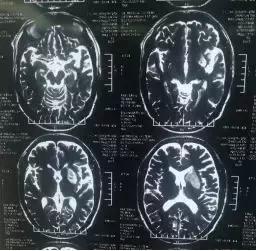

术前MRI示左侧基底节区新发梗塞